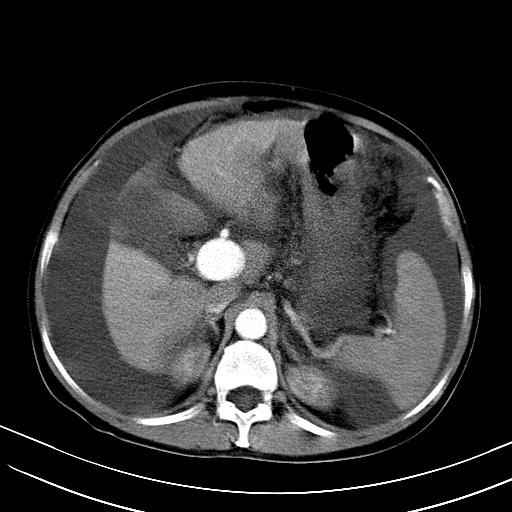

肝动静脉漏,动脉期肝动脉及门静脉内均可见造影剂……

右叶肝癌并肝动静脉漏(动脉期肝动脉及门静脉内均可见造影剂),肝硬化,腹水。(胆囊壁水肿)

1)肝右叶肝癌,考虑并发肝动静脉漏。扫描时间好像慢了。2)肝硬化,门脉高压、脾大、腹水。